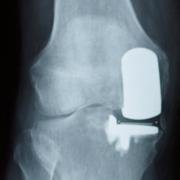

Three compartments

The dotted lines in the illustration artificially cut the femur and tibia to show you that in fact there are two tibiofemoral areas of articulation. There is one patellofemoral compartment, and medial tibialfemoral compartment, and a lateral tibiofemoral compartment.